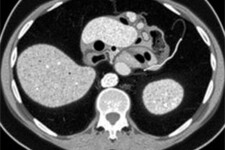

Blinddarmentzündung Radiology Corner: Cómo identificar la apendicitis en una tomografía computarizada